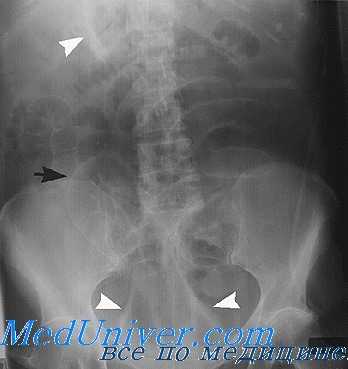

Рентгенологическая картина брюшной полости в норме по данным обзорной рентгеноскопии и рентгенографии.

На обзорном снимке или на флюоресцирующем экране брюшная полость отображается в виде более или менее однородной средней интенсивности теневой картиной на фоне скелета данной области. Это объясняется тем, что органы брюшной полости: печень, селезенка, желудок, кишечник и т. д. имеют одинаковую плотность и рентгенологически не дифференцируются раздельно друг от друга. Но нередко на обзорном снимке бывает видна верхняя часть желудка (так как в ней содержится воздух) — в виде так называемого желудочного пузыря. Иногда бывают видны небольшие скопления газа в петлях тонкого и особенно толстого кишечника — в печеночном и селезеночном изгибах. Прямая кишка часто содержит газ и твердые каловые массы и легко поэтому иногда распознается по своей форме и положению.